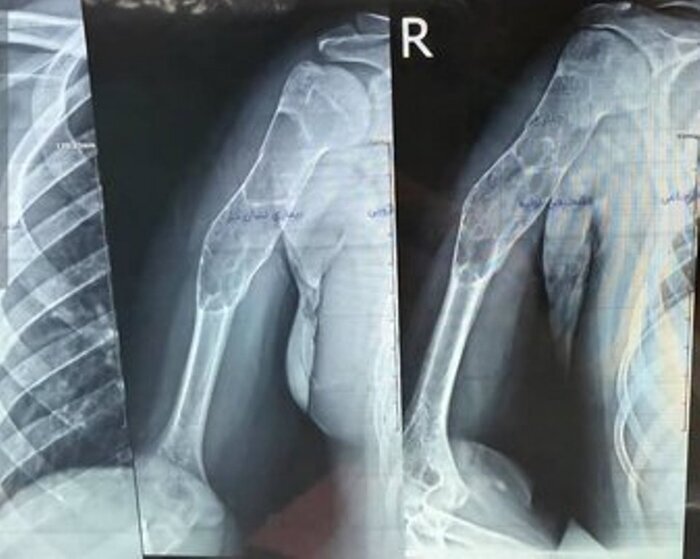

عمل جراحی پیوند استخوان مصنوعی بازو به یک بیمار پسر ۱۶ ساله در پارسآباد مغان با موفقیت انجام شد.

به گزارش خبرگزاری صداوسیما، مرکز اردبیل مدیر شبکه بهداشت و درمان پارسآباد گفت: این عمل جراحی به رغم وجود توده کیستیک وسیع در بازوی این نوجوان، توسط دکتر شهریار خوشبخت جراح و متخصص ارتوپدی و با همکاری تیم جراحی بیمارستان امام پارسآباد صورت گرفت.

دکتر شهریار خوشبخت، جراح و متخصص ارتوپدی هم درباره این عمل جراحی گفت: با توجه به وجود توده کیستیک وسیع در بازوی بیمار، تیم جراحی توانست به مدت سه ساعت پس از عملیات پلاکگذاری، توده وسیع را تخلیه و استخوان مصنوعی را جایگزین کند.